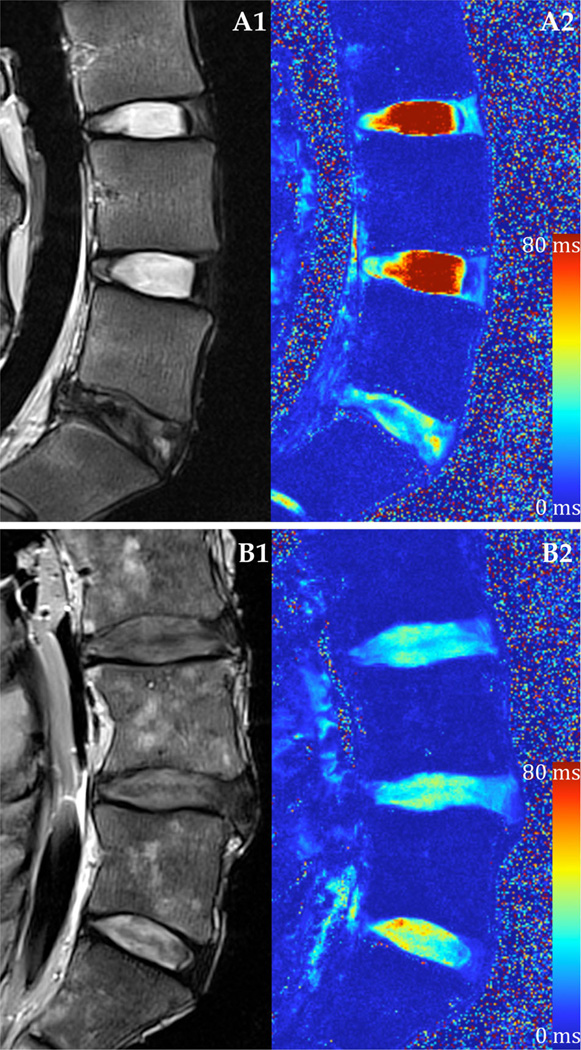

Eighteen human cadaveric lumbar (L4–L5) IVDs (53.2 ± 15.5 years; range: 21–71 years) were imaged using a Siemens 3T MRI scanner (Magnetom Trio; Siemens Healthcare, Erlangen, Germany, Fig. 1). Each specimen was placed in the prone position inside a brain coil where traditional T2 weighted and quantitative T2* MR images were acquired in the sagittal plane. The scans were performed consecutively. To provide context for relative disc health, Pfirrmann grade was assessed independently by seven neurosurgical/orthopedics spine surgeons and 3 Ph.D. level experienced spine researchers based on the T2 weighted MRI.26 These scores were averaged and rounded to the nearest integer. Quantitative T2* relaxation maps (MapIt, Siemens Healthcare, Erlangen, Germany) were obtained using the following imaging parameters [TR(ms): 500; TE(ms): 4.18, 11.32, 18.46, 25.60, 32.74, 39.88; voxel size (mm): 0.5 × 0.5 × 3.0, slices: 33]. Five test sites were isolated across the transverse plane of the IVD, and mean T2* relaxation time was recorded using Osirix Imaging Software at each region of interest (ROI; Fig. 2A). The sites included one in the center NP and four in the AF, including three outer AF areas: anterior (aAF), posterior (pAF), and lateral (oAF), and one inner lateral region (iAF). The lateral test sites were randomized left or right based on a block design based on Pfirrmann grade. A correlational study design was used to examine the relationship between quantitative T2* relaxation time and IVD constituents and residual mechanics properties.

Figure 1.

Representative T2 weighted MRI and T2* relaxation time mapping. (A) Healthy lumbar IVDs and (B) degenerated IVDs using a (1) conventional T2 weighted imaging sequence and (2) quantitative T2* mapping techniques.